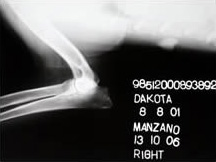

In Memoriam

08.08.2001

Fecha de fallecimiento: 13.04.2011